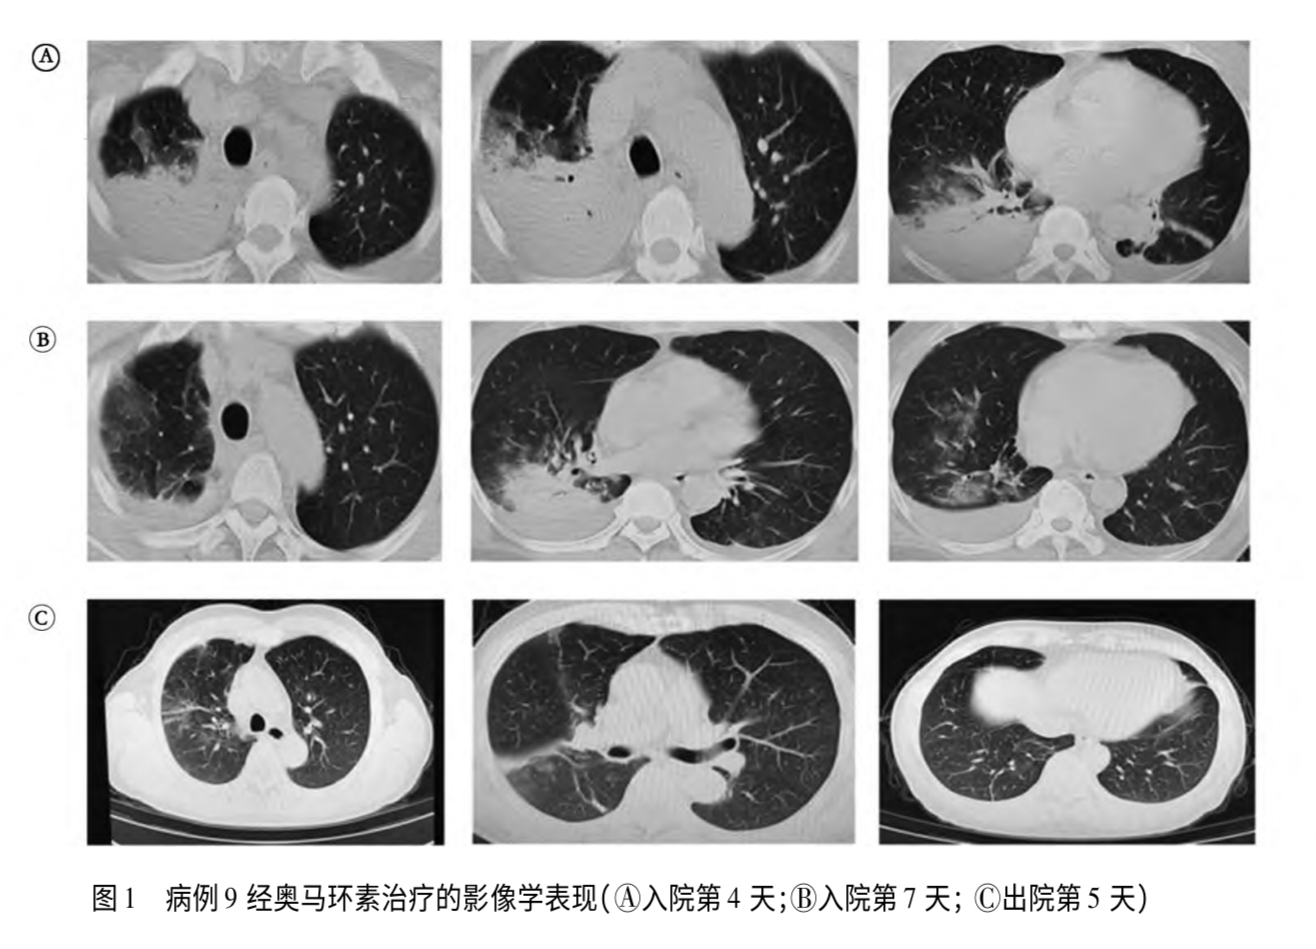

南京医科大学附属南京医院收治的一名鹦鹉热患者影像资料。图/《15例鹦鹉热衣原体肺炎诊疗分析》